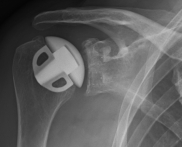

links: X-ray image of a cap prosthesis ("surface replacement")

right: cap prosthesis ("surface replacement", type "Durom" Fa. Zimmer)gkl